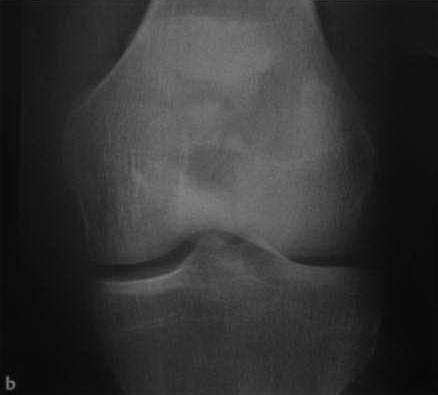

а, b Поперечный закрытый перелом надколенника. Рентгенологическое исследование надколенника в прямой (а) и боковой(b) проекциях.

а,b Оскольчатый перелом надколенника со смещением. Рентгенологическое исследование надколенника в боковой (а) и прямой (b) проекциях. Звездчатый перелом с расхождением фрагментов проксимально и дистально.

На обычных рентгенограммах хорошо определяются переломы надколенника как со смещением и расхождением отломков, так и без него.

- Рентгенологическое исследование коленного сустава в прямой и боковой проекциях, тангенциальная (касательная) проекция надколенника

- Линия перелома

- Могут определяться внутрисуставные свободные тела

Информативность снимков. На снимке в прямой проекции надколенник имеет форму округлого образования, наслаивающегося на изображение дистального метаэпифиза бедренной кости. Структура его видна неотчетливо. На снимке в боковой проекции (рис. 424) хорошо видны основание и верхушка надколенника, передняя и задняя его поверхности, при переломе его определяется расхождение отломков <рис. 425). На снимке в аксиальной проекции (рис. 426) надколенник имеет форму, приближающуюся к треугольной; передняя его поверхность выпуклая, контур ее четкий и неровный..png)